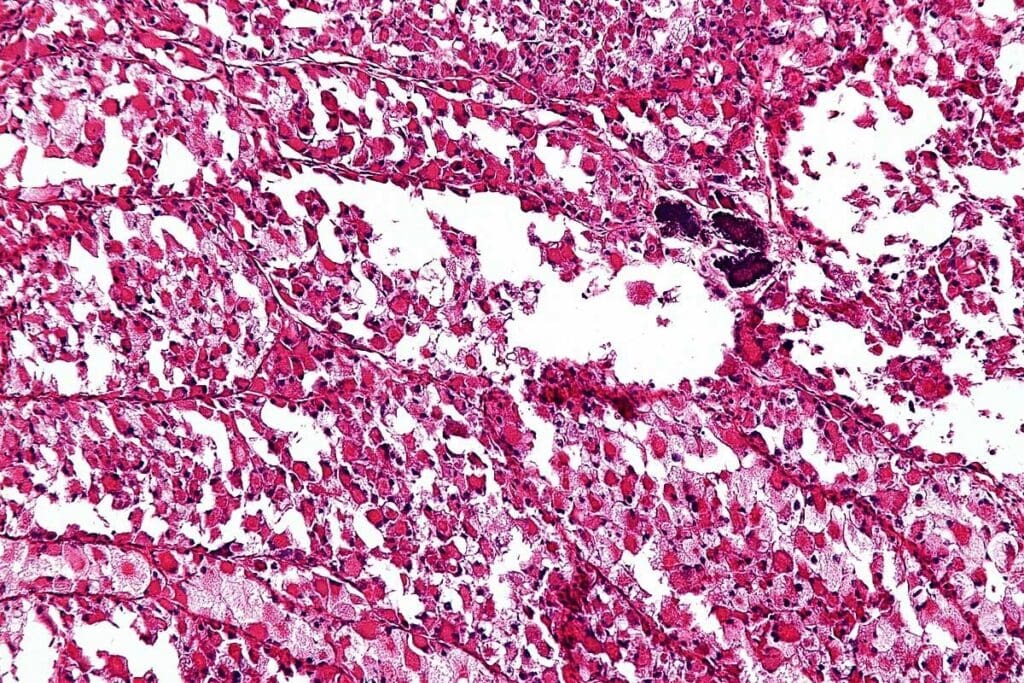

Ewing sarcoma is a cancerous tumor known for its aggressive nature. It mainly affects younger people. This type of cancer comes from a specific cell in bones or soft tissues.

Ewing sarcoma is a highly malignant tumor that mostly hits teens and young adults. Epidemiologically, it’s a rare disease, more common in males than females. The exact cause is unknown, but genetic mutations are thought to play a role.

T1-Weighted Image Characteristics

On T1-weighted images, Ewing sarcoma looks like a low to intermediate signal lesion. This helps doctors see where the tumor starts and stops. It also shows how it relates to nearby structures.

T2-Weighted Image Characteristics

T2-weighted images are great for looking at the tumor’s soft tissue part. Ewing sarcoma shows up bright on these images because of its water content. This makes it easier to see how it affects the surrounding tissues.

Contrast Enhancement Patterns

After contrast material is given, Ewing sarcoma shows uneven enhancement. This means different parts of the tumor light up differently. This unevenness can tell doctors about the tumor’s blood flow and any dead areas.

Knowing these MRI signs is vital for diagnosing Ewing sarcoma. It helps doctors tell it apart from other tumors. MRI details help in planning the best treatment for the patient.